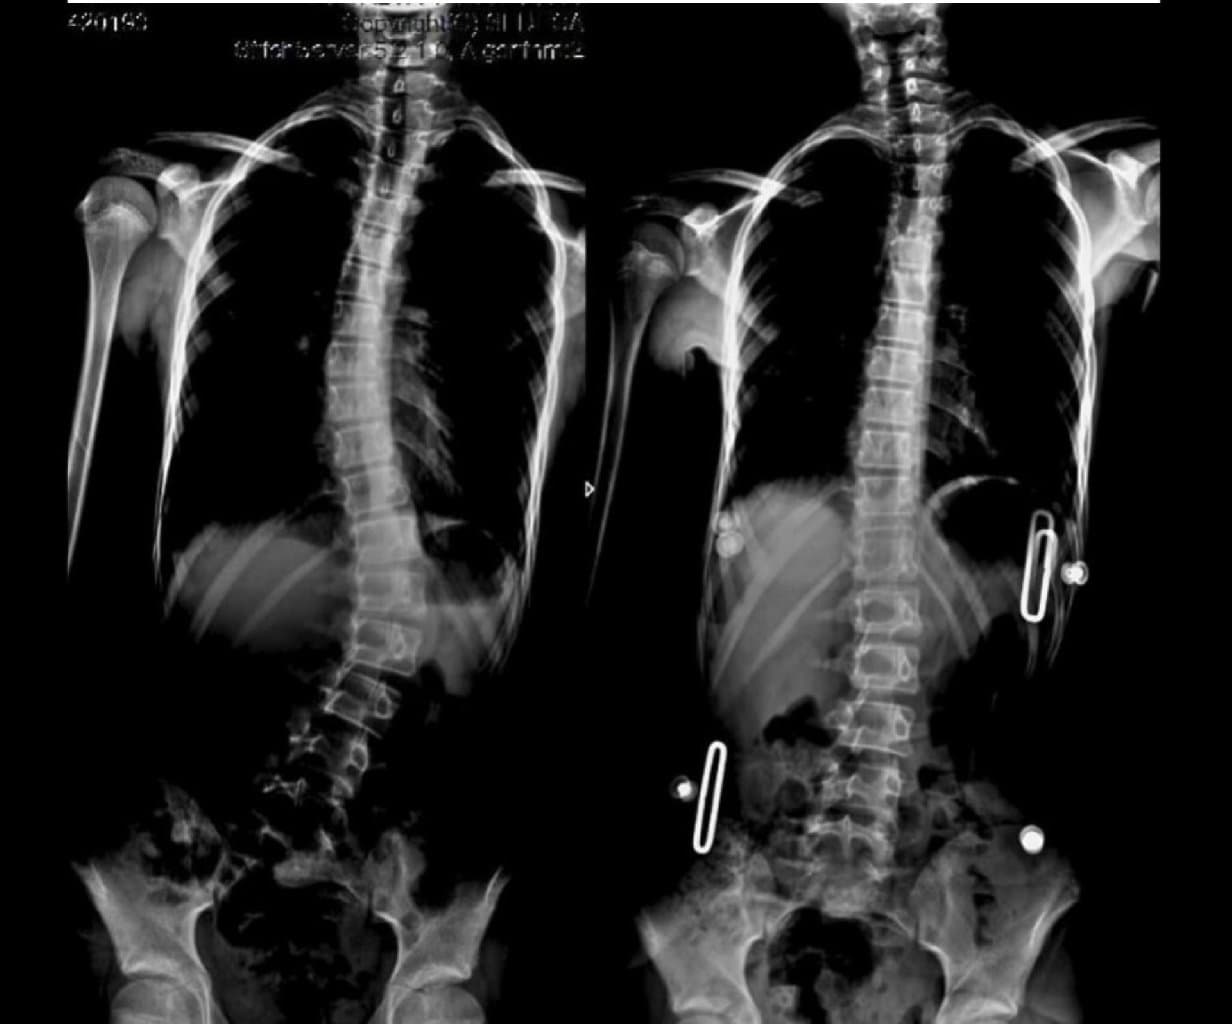

Bel sütununun funksiyalarına müəyyən bədən toxumalarının struktur dəstəyi, hərəkəti və qorunması daxildir. Bel ağrılarına buradakı onurğa sümükləri, fəqərələr arasındakı disklər, onurğanın ətrafındakı bağlar, onurğa beyni və sinirlər, bel ətrafındakı əzələlər, qarındakı daxili orqanlar və bel nahiyəsini örtən dəri səbəb ola bilər.

Bel ağrılarının 95%-i mexaniki səbəblərdən qaynaqlanır. Mexanik bel ağrısı bel nahiyəsində heç bir problem olmadan bel əzələlərindən və ya ətrafdakı birləşdirici toxuma və yumşaq toxumalardan, onurğa və oynaqların ətrafındakı sinir toxumalarından yaranan ağrılara verilən addır. Ağrı ombalara yayıla bilər, ancaq dizdən aşağı deyil. Günümüzdə müasir texnologiya ilə fərdlərin gündəlik fəaliyyətləri zamanı buraxdıqları səhvlər bel ağrılarının tezliyini artırıb. Səhv oturmaq, kompüter qarşısında işləmək kimi hallar fərdlərin duruşunu pozur, arxa əzələlərini zəiflədir və uzun müddətdə bel ağrılarına səbəb olur. Siqaret çəkmək beldə olan fəqərələr arasında amortizator rolunu oynayan birləşdirici toxumanın qan tədarükünü və strukturunu pozaraq yırtıq əmələ gəlmə ehtimalını artırır. Həddindən artıq çəki və uzun müddətli qəbizlik də onurğaya təzyiq göstərərək struktur pozğunluqlarına səbəb ola bilər. Çağımızın ən böyük problemlərindən biri olan oturaq və idmansız həyat, bel sağlamlığının ən əhəmiyyətli komponentlərindən biri olan bel əzələlərini zəiflədir və uzun müddətdə xroniki bel ağrılarına səbəb olur. Hamiləlik, stress və depressiya kimi psixososial faktorlar da əhəmiyyətli səbəblər kimi görünür.